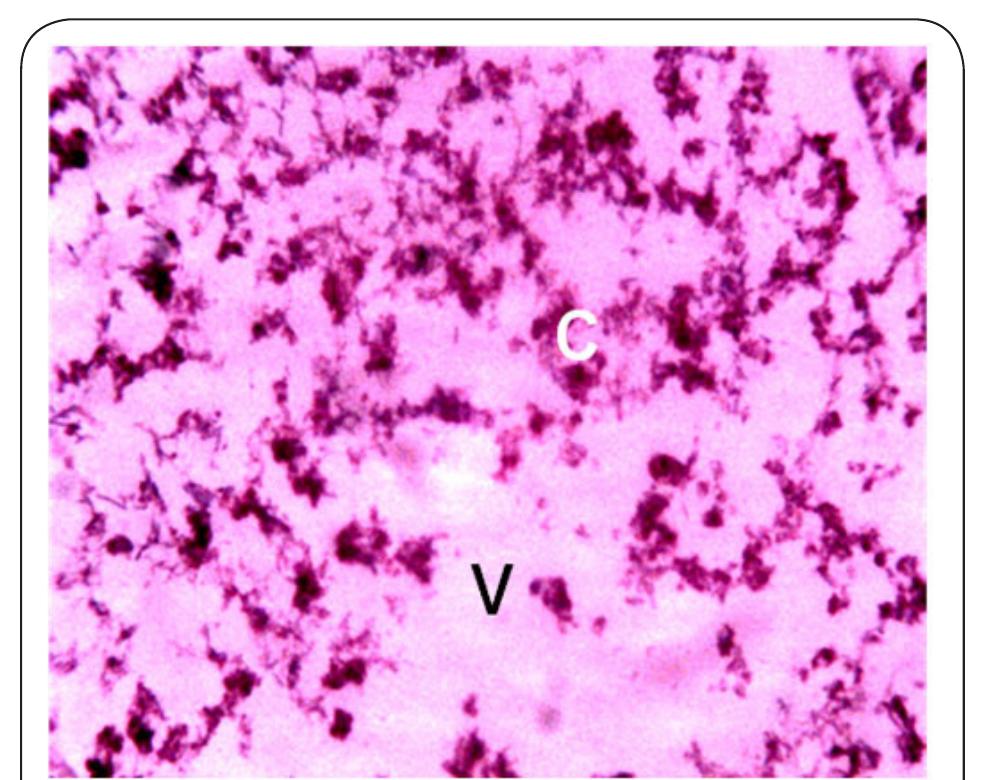

Dr. Ozovehe Patrick Samuel - FEDERAL UNIVERSITY OF TECHNOLOGY, MINNA-NIGERIA